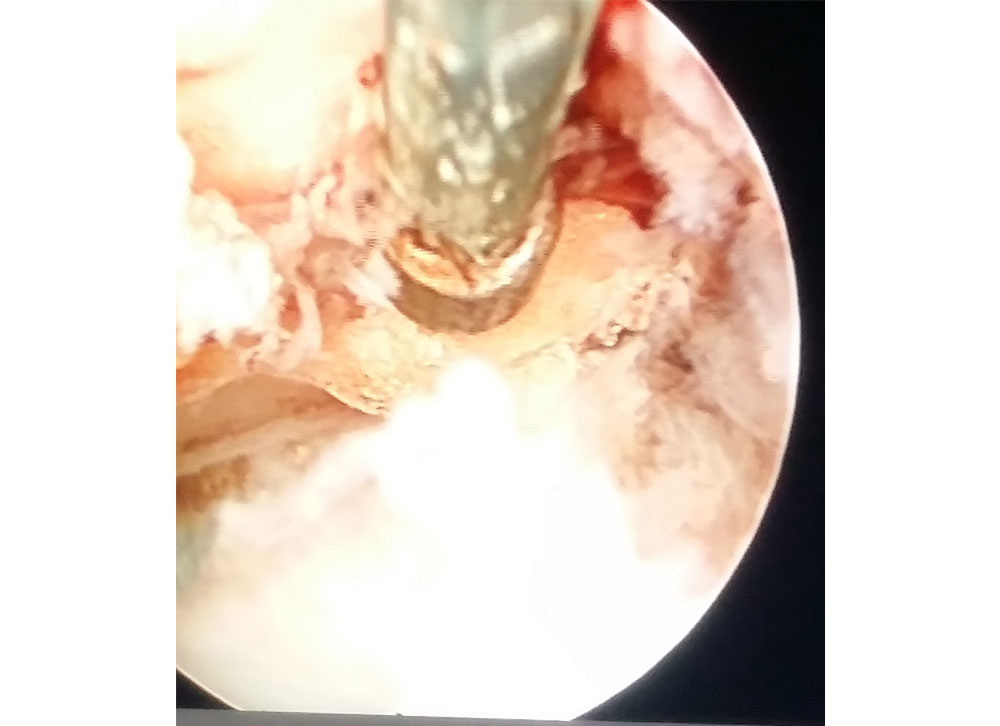

Endoscopic view of spinal canal

Endoscopic surgery in progress